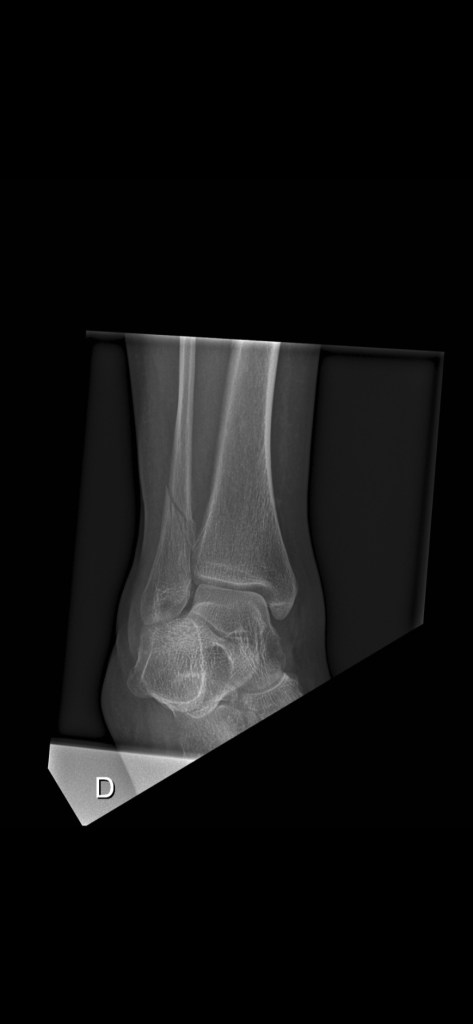

Ich habe einen neuen. Einen sogenannten Gehgips. Aus Plastik und zum Auftreten. Mit Anpassung vom Chef-Orthopäden und Röntgenbildern, die mit Auftreten im Stehen gemacht wurden. Allerdings plagen mich Kopfschmerzen des Todes. Als Trostpflaster haben die Kids gekocht – Mamas Lieblingsessen: Vol-au-vent mit Fritten und Königinpastete, Bouchée à la reine. Das Vol-au-vent gibt’s von Lidl in Belgien im Glas. Das ist hier das Ravioli (ich hasse Ravioli) für Leute, die schnell kochen müssen. Lecker und ein Trostpflaster.

Verband auf belgische Art- Gips Teil 3

Die Herrschaften in der Notaufnahme waren wirklich sehr nett. Haben mir erklärt, dass eine aufblasbare Schiene nicht so sinnvoll wäre, wie ein oldschool Gips. Mit Verband. Okay. Die sind immer sehr freundlich da und ich meckere ja nicht. Er ist nur sooo schwer und das ist echt … sch….

Der Gips- Teil 2

Ich sitze im Bett, weil schon das kleinste Bewegen meines Gipsbeins zuverlässig zur schmerzhaften Grundsatzdiskussion führt. Also bleibe ich liegen. Aus reiner Vernunft – und weil Tramal allein keinen Heldenroman schreibt.